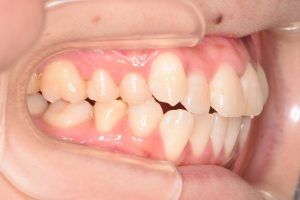

右側

問題点

・叢生

・右上犬歯低位唇側転位

・下顎骨の後方位による上顎前突

・下顎前歯部唇側傾斜

・右側第二大臼歯部シザーズバイト

両側の犬歯が咬みあっていないので

奥歯にとても負担のかかる咬合状態でした。